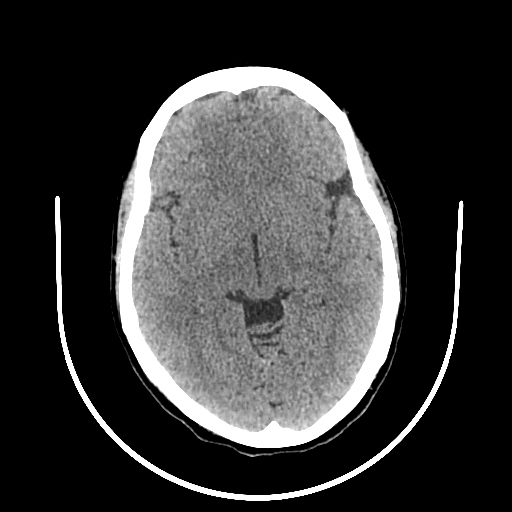

A 33 years old woman with protruding eyeballs & hyperthyroidism since 2 years